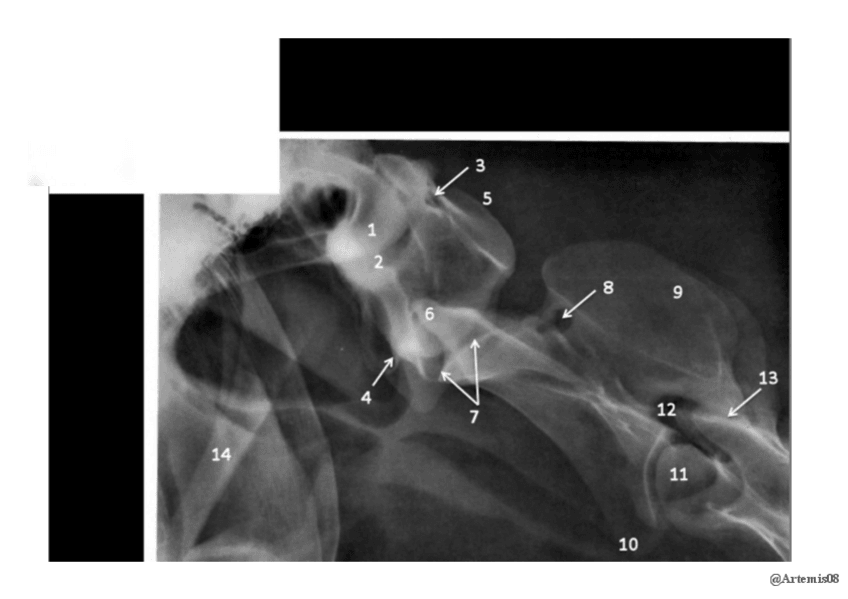

He publicado nuevos apuntes de 1º EMBRIOLOGÍA Y ANATOMÍA I: Radiografías práctica 6.pdf

8 páginas

He publicado nuevos apuntes de 1º EMBRIOLOGÍA Y ANATOMÍA I: Radiografías práctica 3.pdf

5 páginas

He publicado nuevos apuntes de 1º EMBRIOLOGÍA Y ANATOMÍA I: Radiografías práctica 5.pdf

10 páginas

He publicado nuevos apuntes de 1º EMBRIOLOGÍA Y ANATOMÍA I: Radiografías práctica 7.pdf

13 páginas

He publicado nuevos apuntes de 1º EMBRIOLOGÍA Y ANATOMÍA I: Radiografías práctica 8.pdf

12 páginas

He publicado nuevos apuntes de 1º EMBRIOLOGÍA Y ANATOMÍA I: Radiografías práctica 4.pdf

9 páginas